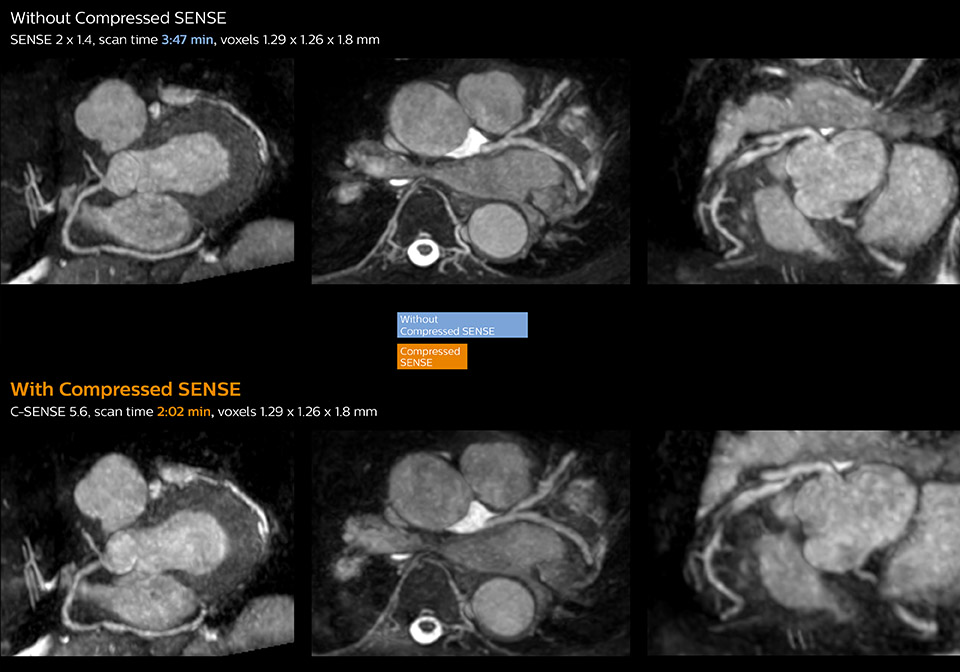

“Compressed SENSE has now been implemented in all cardiac exams. Thanks to the acceleration, fewer breath holds are now needed, or breath hold times are shortened. This reduces the burden of the exam for cardiac patients, without affecting the quality of information required for cardiac function analyses,” he says. “Because it’s easier for patients to comply with the breath hold times” “In our previous cardiac cine sequence, we were acquiring two slices during one breath hold. With Compressed SENSE, we increased this to four slices per breath hold. It is also possible to shorten scanning time using a C-SENSE factor 6 without sacrificing image quality.”

Dr. Koshi Miyake, cardiologist, explains that scanning of patients with cardiac arrhythmia can be challenging, as scanning times can become very long due to the varying heart rate. So his most important motive to implement Compressed SENSE in cardiac MRI exams was to reduce the burden of breath holds for the patient, while maintaining high image quality. He hopes this can also help to reduce motion caused by the difficulty for patients to hold their breath.

“Typically, in scans with high contrast, such as 2D balanced TFE cine, a quite high C-SENSE factor may be used. When we tried a higher C-SENSE factor, we saw still no significant influence on cardiac ejection fraction, but 2D image quality started to decline. For coronary imaging, we use a C-SENSE factor of 3 in 3D balanced TFE, or even up to 4 when contrast is high.”

These images of a patient with acute myocardial infarction images were acquired on Ingenia 1.5T with and without Compressed SENSE.